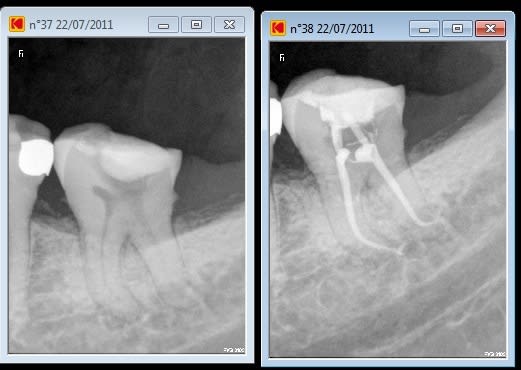

une ptite 38 de l'après midi (sans digue o pas bien fouilla !) mais j'avais oublié de faire la rétro avant dépose de la capote

en numéro deux radio d'une patiente qui s'était barrée avec mes endos et des inlays cores et qui revient 5 ans après ! je me 'en souvenais plus et je m'étais bien fait rire sur celles la( hero 6 4 2 je crois à l'époque)

25 en 06 ou 07?

45 non 25 pour le reste pas de memoire

tu l'as vu dans le canal distal le fragment de l'hero